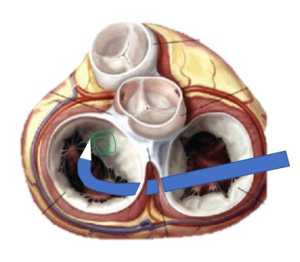

- La mesure des surfaces des orifices mitraux (médial et latéral) suite à la pose d’un premier clip est une étape clé dans la prédiction du risque de sténose.

Face à un risque de sténose lors du placement du clip, il est toujours possible de repositionner le clip en l’éloignant du centre de l’orifice, avec un effet immédiat de diminution du gradient trans-mitral.